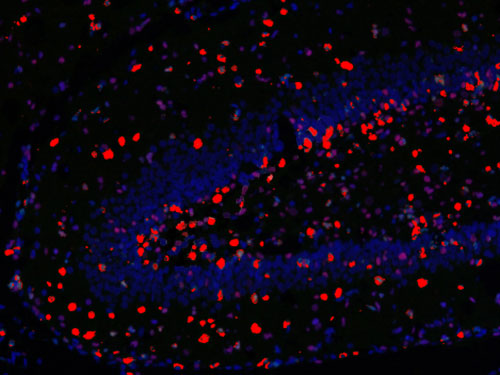

□免疫熒光多標陽性共定位分析:

測量整張掃描切片或者指定區域中單獨通道的數據以及指定共定位的數據(陽性面積或陽性率值表示,選其一)。

免疫熒光空間距離分析:

主要用來研究腫瘤微環境,炎性細胞和腫瘤細胞之間的距離關系等。

□分析一種指標標記的細胞周圍多少微米范圍之內另一指標標記的細胞數量,可以設置不同范圍;

□分析不同指標標記細胞之間的平均距離;

□以某處為界(如腫瘤灶、壞死灶或指定區域等)分析該區域多少微米范圍之內不同指標標記的細胞數量,例如腫瘤周圍500um內CD3陽性細胞的數量。